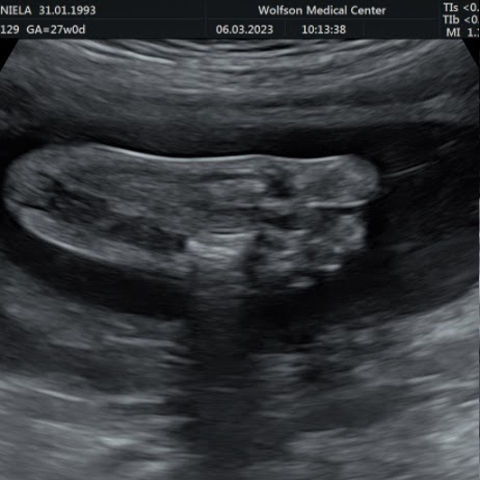

גלריה